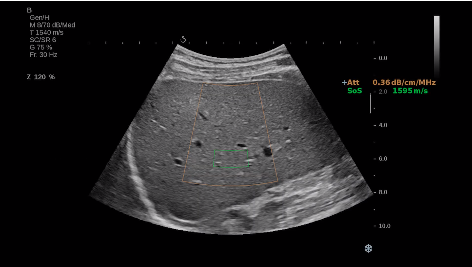

法國(guó)聲科影像(SuperSonic Imagine,SSI. Euroniex:FR0010526814)近日發(fā)表公告,宣布其研發(fā)的新一代“極速”超聲成像平臺(tái)(UltraFast Imaging),首次實(shí)現(xiàn)了肝臟的多項(xiàng)超聲定量評(píng)估新指標(biāo)同步檢測(cè),包括:Att PLUS,SSp PLUS和Vi PLUS等,基本涵蓋肝臟相關(guān)病理變化指征的如纖維化、脂肪變、炎癥等。據(jù)悉,此多項(xiàng)新技術(shù)新將搭載于新Aixplorer系列E超系統(tǒng)。

E超相關(guān)技術(shù)已被多項(xiàng)多中心大樣本研究證實(shí)對(duì)于肝纖維化無(wú)創(chuàng)評(píng)估有重要意義,同時(shí)也可全面應(yīng)用于乳腺、甲狀腺、肝臟、前列腺、肌骨、婦科等全身各組織器官的定量評(píng)估和鑒別診斷。在慢性肝臟方面,聲科E超的肝臟相關(guān)定量診斷技術(shù)集,于2018年獲得美國(guó)FDA認(rèn)證,成為FDA歷史上首次獲批的單病種超聲全面定量解決方案。

E超是在原有B超、彩超(彩色多普勒CDFI)基礎(chǔ)上研發(fā)成功的新一代超聲剪切波彈性成像系統(tǒng),是一種能夠全面應(yīng)用于表淺組織、腹部臟器,血管等方面的組織彈性成像技術(shù)。根據(jù)組織硬度彈性值的不同,有效鑒別實(shí)性腫瘤的良惡性。對(duì)于惡性病變的診斷具有較高的特異性和敏感性,尤其對(duì)于甲狀腺、乳腺、前列腺等小器官,能夠完成常規(guī)超聲不能完成的組織定量分析,可以實(shí)時(shí)、全幅、全定量獲得組織彈性(硬度)信息,為鑒別腫瘤的良惡性提供客觀、量化的診斷依據(jù)。